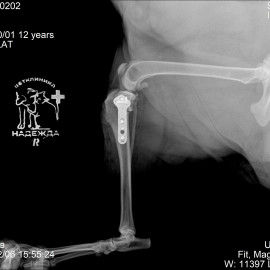

Была проведена операция - TPLO.

Снимок 2 после операции.